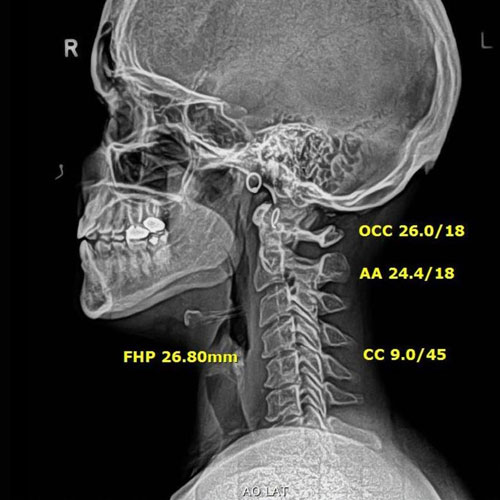

In this case, initial cervical spine X-rays revealed a significant loss of normal neck curvature, a condition that places excessive strain on the spine and nervous system. When the cervical curve is reduced, the head shifts forward, increasing stress on spinal joints, discs, and nerves — often leading to chronic neck pain, headaches, migraines, and neurological symptoms.

Before Chiropractic Treatment: The patient’s X-rays showed a flattened cervical curve, meaning the neck was no longer supporting the head in its ideal position. This type of misalignment is commonly linked to long-term spinal degeneration, nerve irritation, and persistent symptoms that don’t resolve with medication alone.

After Corrective Chiropractic Care: Following a customized course of corrective chiropractic treatment, repeat X-rays demonstrated measurable improvement in cervical alignment. More importantly, those structural changes translated into real-life results — reduced pain, improved function, and a return to daily activities with confidence.